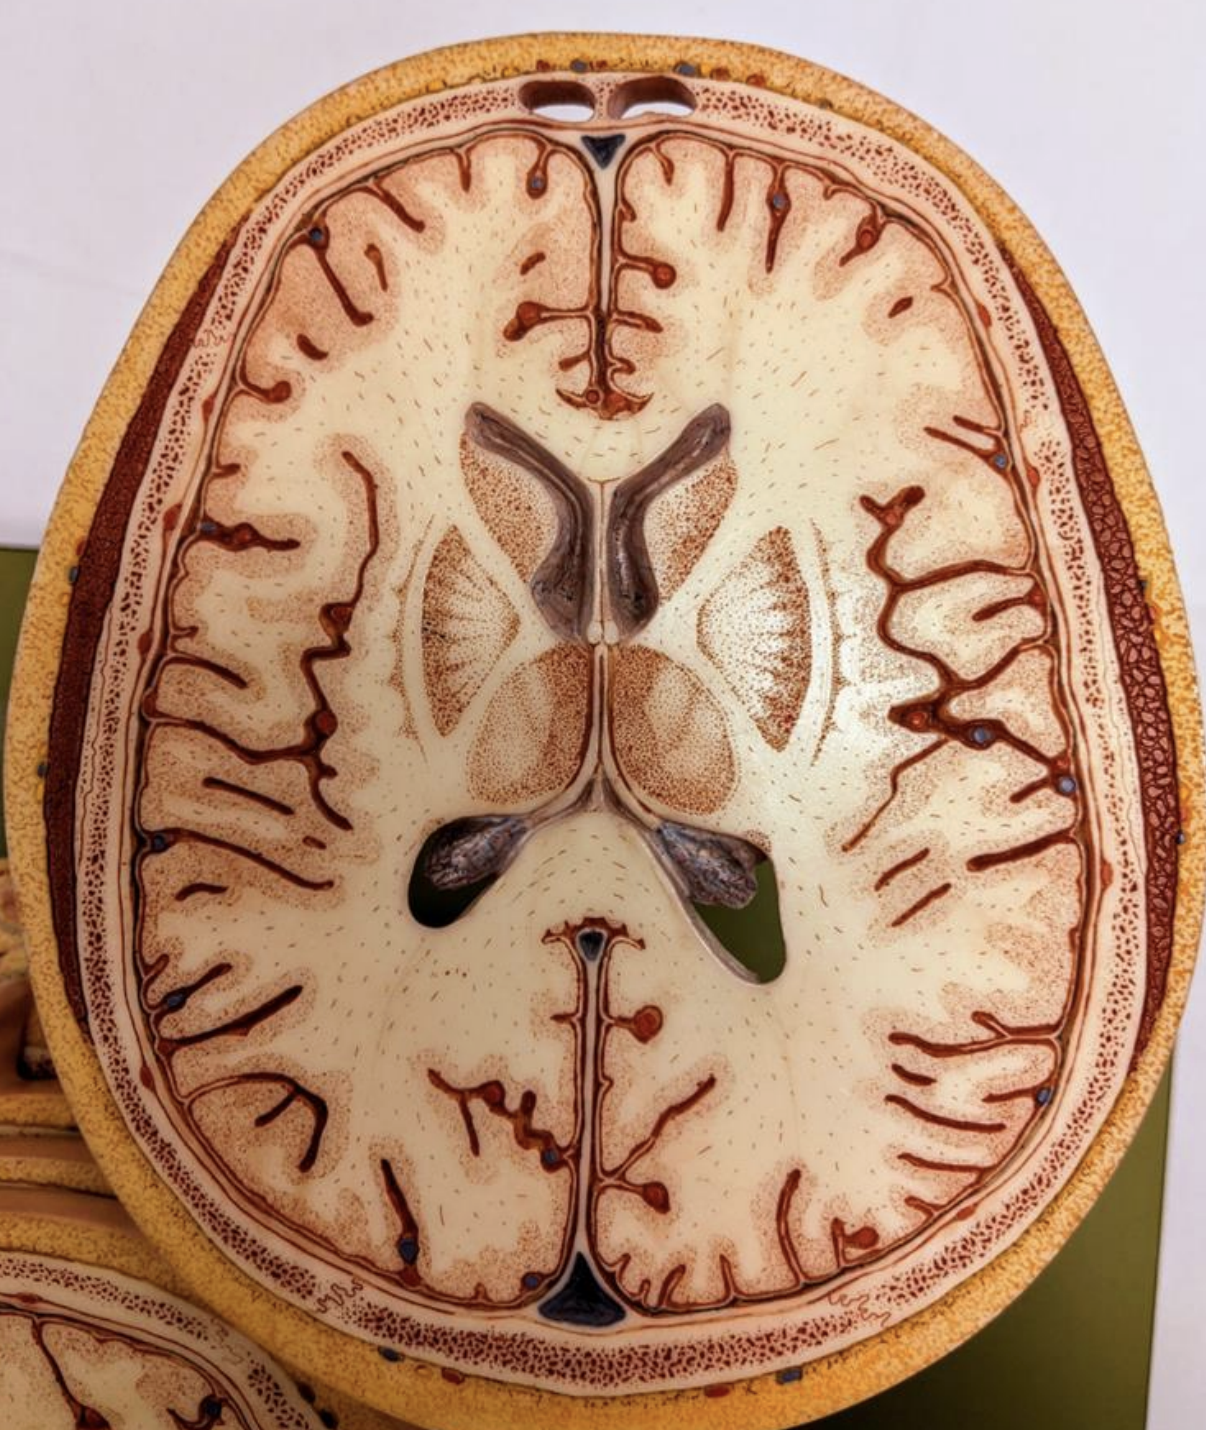

The lateral ventricle:

Anterior (frontal) horn

Body

Posterior (occipital) horn

Inferior (temporal) horn

Interventricular foramen

Head, body and tail of caudate nucleus - top

Putamen - middle

Nucleus accumbens - bottom

Stria terminalis - between caudate nucleus and lateral ventricles

Lenticular nucleus

Internal capsule

Thalamus

External capsule

Claustrum

Extreme capsule

Insula

Head and tail of the caudate nucleus

Globus pallidus

Putamen

External capsule

Claustrum

Extreme capsule

Body and splenium of corpus callosum

Anterior and posterior horns of lateral ventricles

Choroid plexus

Septum pellucidum

Fornix

Insula

Lateral fissure